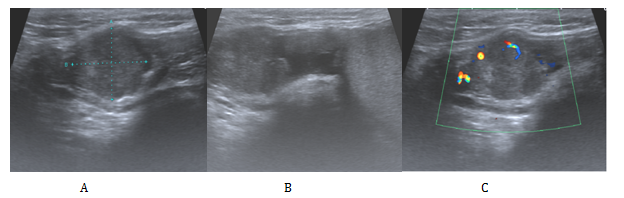

As a result of the histological findings a subsequent CT Chest/Abdomen/Pelvis was organised, this showed no evidence of residual or metastatic disease. The case was then discussed in the oncology MDT. The decision at that point given the diagnosis of malignant mesothelioma which offers a high risk of recurrence was to offer adjuvant chemotherapy with Cisplatin Pemetrexed. He was subsequently closely followed up by the clinical oncologist at 3-6 monthly intervals. Unfortunately 13months after his chemotherapy he presented in clinic with a right inguinal mass. On examination this was overlying his right pubic bone extending down the line of the inguinal canal and into the superior aspect of his right hemiscrotum. His US and CT (Figure 3) confirmed a 9x4.5x4 cm multilocular malignant mass consistent with local recurrence. He subsequently received a high dose palliative radiotherapy to the recurrence (40Gy 15 fractions).

Figure 3 Cross section tomographic appearance of the recurrence in the right groin in the transverse (A) and coronal (B) planes.